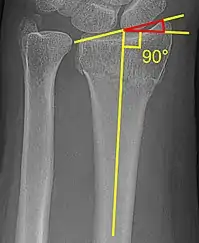

Volar vs dorsal tilt

A dorsal tilt of a distal radius fracture is shown in red in image at right. The angulation goes between:[1]

1. A line drawn between the distal ends of the articular surface of the radius on a lateral X-ray.

2. A line that is perpendicular to the diaphysis of the radius.

Sometimes, the diaphysis of the radius is hard to distinguish from the ulna, and a line between them (turquoise line in image) may be used instead.[2]

Fracture with a decreased radial inclination (about 15°).